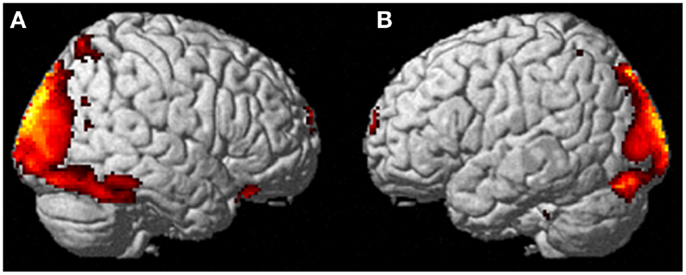

It’s important for readers to understand that the fMRI paper is not an experiment with a hypothesis, like “people can leave their bodies and float around the room,” that has been tested in a double-blind scenario, like “once the subject was asleep, a playing card was placed next to them and removed before they woke. They were asked to name the card they saw during their out-of-body experience”, and been shown to be statistically valid, like “8 out of 10 times the subject was able to correctly identify the playing card,” and been peer reviewed and then published in a journal. Instead, this is the case of a person who claims to be able to leave her body at will, so researchers stuck her in an fMRI machine and looked at what happened to her brain when she was having this experience/hallucination.

The word “hallucination” appears ten times in the case study yet zero times in the Popular Science article. Because of this, a naive person who reads the PopSci article but not the original paper may walk away with the belief that the brain scans show what happens when a person actually leaves their body, as opposed to showing what happens when a person feels as though they are leaving their body. Again, the difference seems small but is actually quite large: the former describes a study that would be at home on an episode of Coast to Coast or Fringe or those episodes of Family Matters where Urkel did science experiments, and the latter would be at home in a scientific journal to be used as the basis for further study and experimentation.